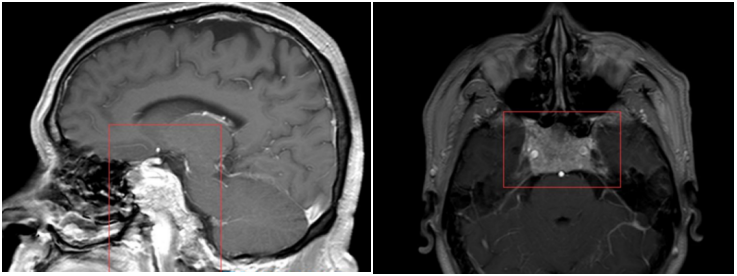

2.脊索瘤:脊索瘤起源于胚胎残留的脊索组织,从rathkes憩室扩展至斜坡,继续向下累及尾部的椎体。典型的斜坡脊索瘤的特点为居中线区的肿块,内见部分钙化,破坏斜坡骨质,并可见软组织肿块突入蝶窦或鼻咽。

3.软骨肉瘤:软骨肉瘤发生部位不一,常与颅缝相关。在岩斜区,其通常发生于岩枕缝。大部分颅面部的软骨肉瘤是低级别的,其罕见、生长缓慢、局部侵犯。